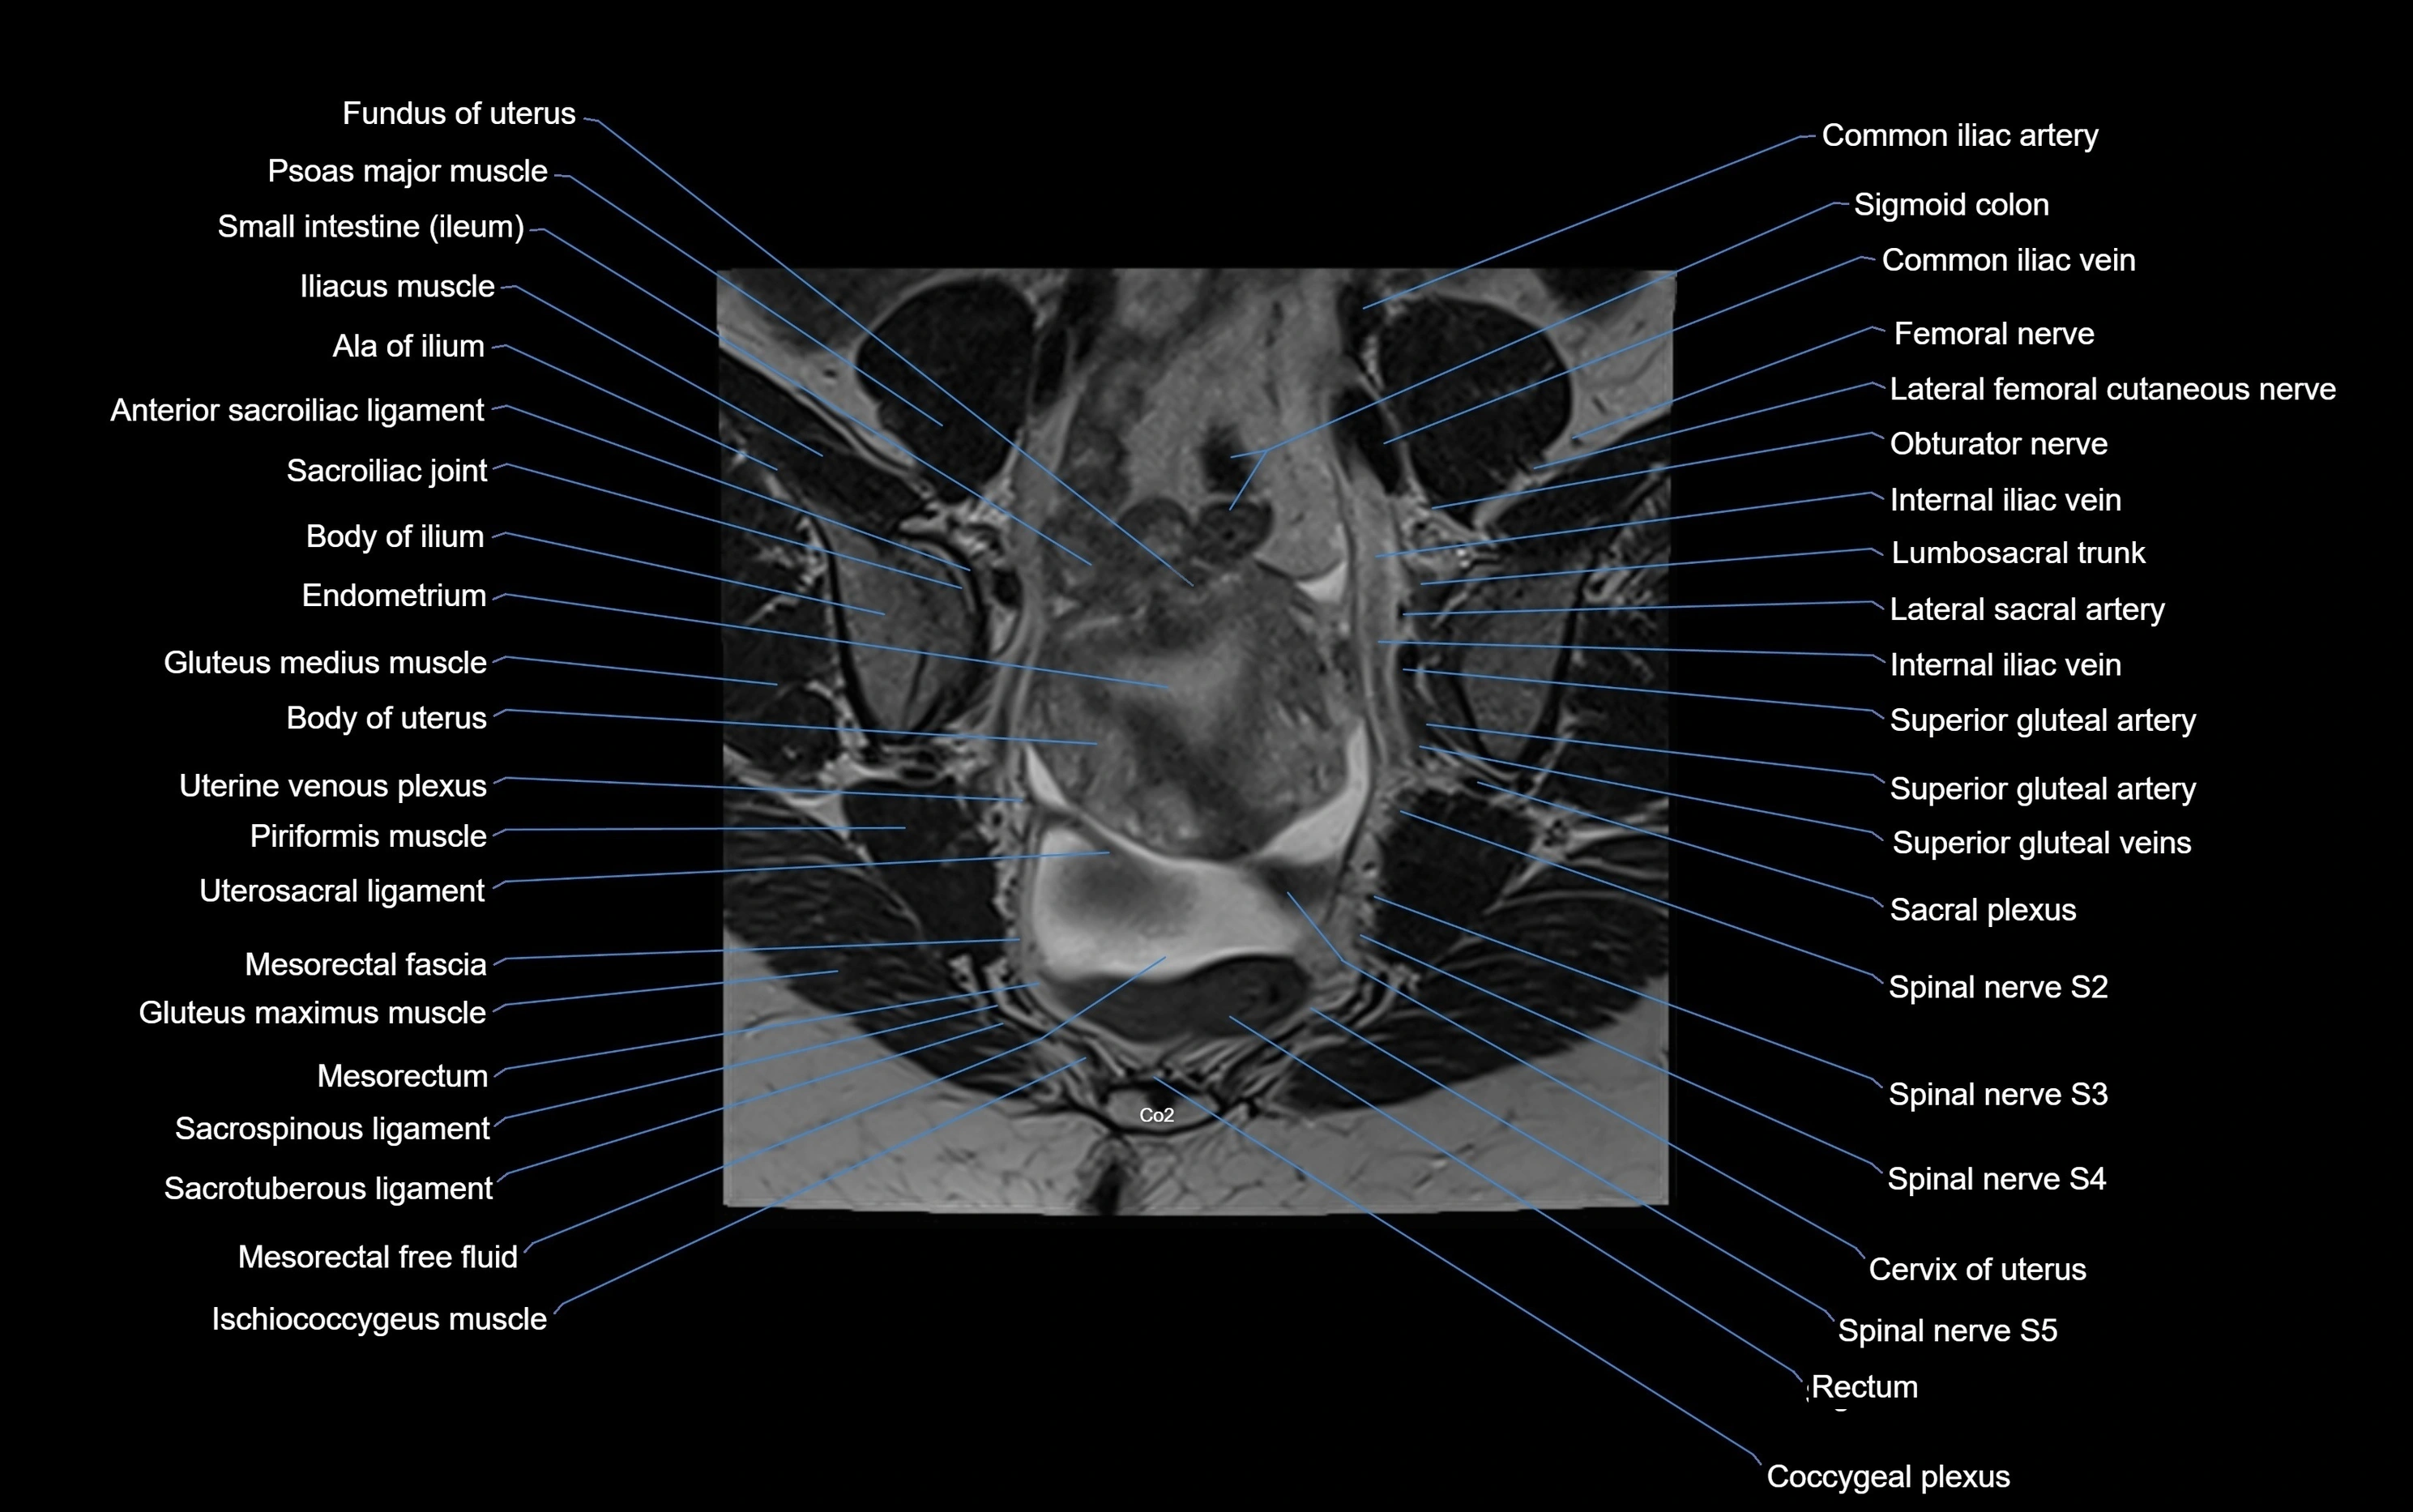

MRI Appearance

T1-weighted images:

• Cortical bone appears very low signal (dark); marrow shows intermediate signal

• Iliac fossa fat is bright against low-signal cortex

T2-weighted images:

• Cortical bone remains dark

• Marrow signal varies depending on fat content; edema or tumor shows hyperintensity

STIR:

• Suppresses fat, making bone marrow edema, fractures, or infiltrative lesions appear bright

• Excellent for trauma, sacroiliitis, and metastatic evaluation

T1 Fat-Saturated (Pre-contrast):

• Marrow: intermediate signal, fat suppressed

• Useful for detecting subtle marrow abnormalities adjacent to iliac cortex

T1 Fat-Saturated Post-Contrast (Gadolinium):

• Enhances vascularized structures, marrow pathology, tumors, and inflammatory changes

• Highlights soft tissue or bone invasion in pelvic neoplasms

MRI Non-Contrast 3D Imaging:

• Provides 3D morphology of iliac wing, crest, and articulations

• Used in preoperative planning for pelvic surgery and trauma reconstruction

MRI image

image